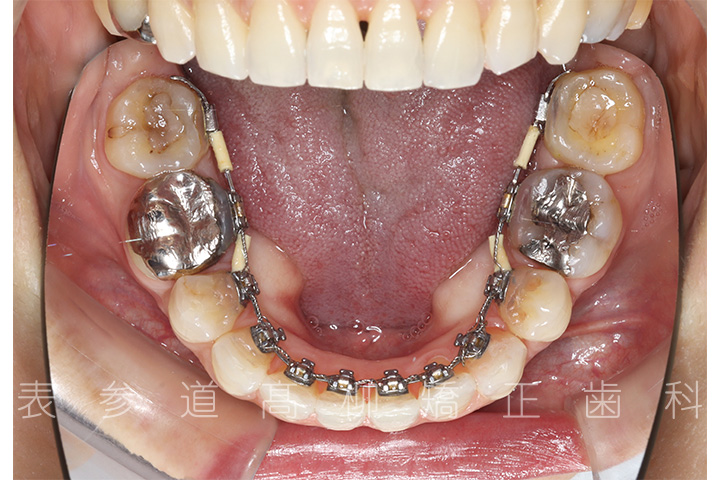

上下4本第二小臼歯抜歯症例

口呼吸と舌癖で前歯が咬み合わない患者様の症例をご紹介いたします。

治療経過

• 治療開始

・上下両側第二小臼歯を抜歯

・マウスピース型矯正装置と歯科矯正用アンカースクリューを併用し、上顎臼歯部を圧下

・歯科矯正用アンカースクリュー(i-station)を併用し、前歯部を後方へ移動する

・歯科矯正用アンカースクリューを併用し、下顎大臼歯の近心移動(前方への移動)

・上下歯列の緊密な咬合関係の確立に顎間ゴムを併用(装着時間20時間以上/日)

・マウスピース型矯正装置よる嚙み合わせの微調整

・MFT(口腔筋機能療法)

・リンガルブラケット装置

・歯科矯正用アンカースクリュー(i-station)

・マウスピース型矯正装置